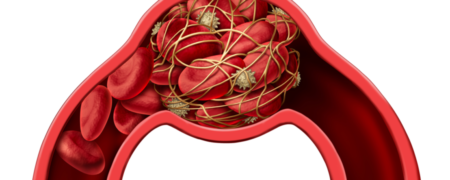

لخته شدن خون می تواند در سیاهرگ ها یا شریان ها ایجاد شود. هشدارهای اولیه این عارضه شامل گرفتگی، تورم یا گرماست. اما دو علامت جدی دیگر وجود دارد که...

علائم لخته خون که هرگز نباید نادیده بگیرید: از تغییرات در نفس کشیدن تا رنگ پوست